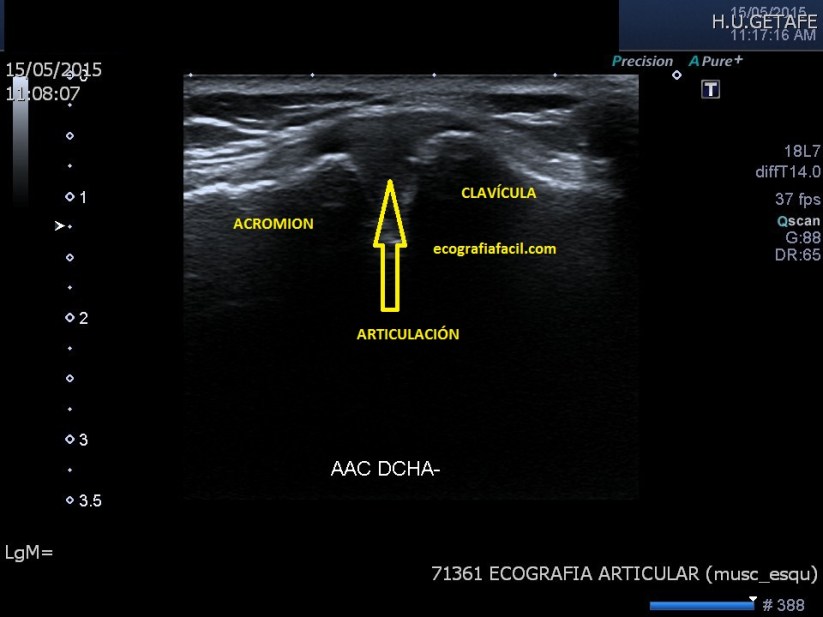

Articulación Acromio-Clavicular.